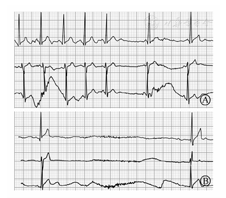

患者男性,13岁,因"间断意识丧失2年"于2015年10月9日入院。患者2年前练习击鼓过程中突发意识丧失,伴呼吸心跳骤停、口吐白沫、小便失禁,立即心外按压,外院予以电除颤、气管插管、呼吸机等治疗后恢复,查心电图未见明显异常,未进一步诊治。入院前半个月于打球过程中再次出现意识丧失,伴心悸、四肢抽搐、口吐白沫,持续2 min自行恢复,好转后除轻度稍头晕外无其他明显不适。外院行心电图、心肌酶、头颅磁共振检查均阴性;Holter示总心搏84 265次,最慢30次/min,平均64次/min,最长QTc 479 ms,间歇二度及高度窦房传导阻滞(图1A)、短暂窦性停搏(最长5.9 s,21∶11,自述当时呕吐中,无其他不适)(图1B),可见交界及室性异搏。就诊我院以"意识丧失待查"收入院。既往体健,个人、生长发育、家族史无特殊。查体:一般情况好,心率77次/min、血压106/84 mmHg,双肺(-),心界不大,心律齐,未闻及心杂音和附加心音、未闻及P2亢进,腹部(-),双下肢不肿。

A:二度Ⅱ型窦房传导阻滞;B:5.9 s窦性停搏